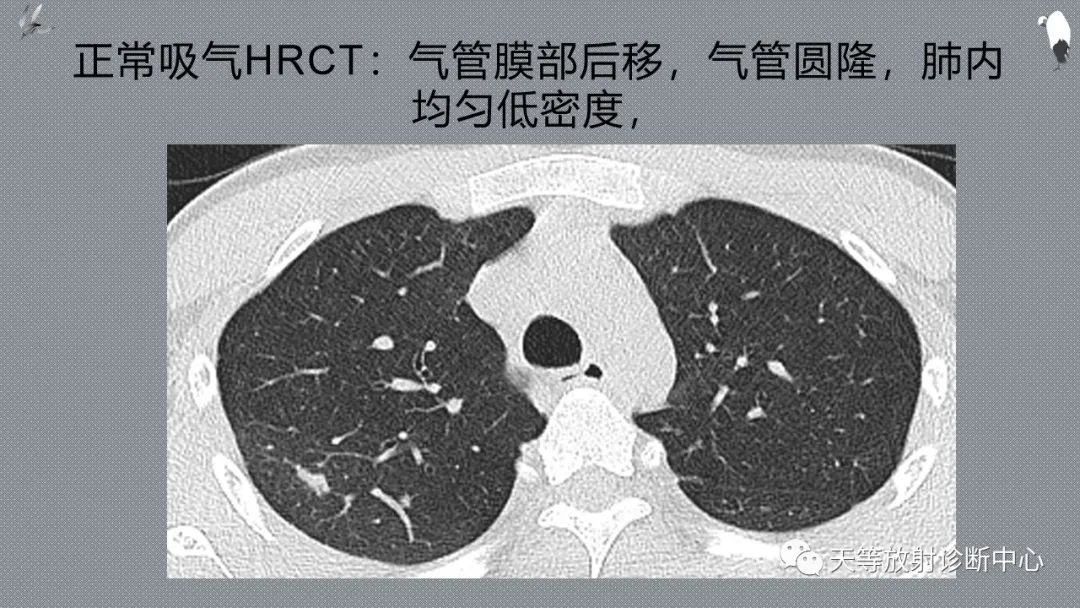

正常吸气及呼气HRCT表现—探索小叶性含气增多影像学

CT可以观察到底是吸气状态还是呼气状态的图像,这有利于对肺内气体量的评价。

充分吸气后进行CT扫描,有利于把肺内正常的含气组织和高密度的肺间质结构进行区分,利用充分显示病灶。

更清楚显示肺血管、支气管气道影像、胸膜及叶间胸膜